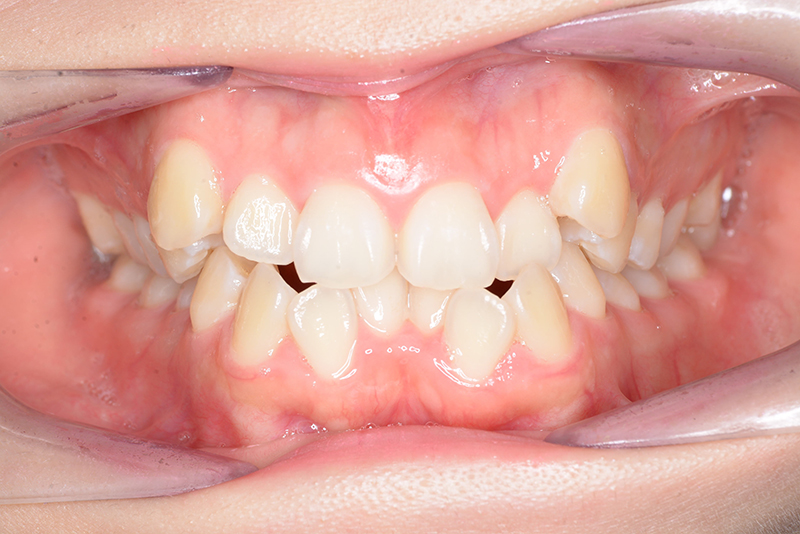

| 批評・予后 | 叢生が大きかった影響もあり、治療期間は20ヶ月と比較的短い期間が終了できた。治療後においては口元の改善、咬合の緊密化は達成できたように思う。 |

| 口腔内所見 | over jet 4.5mm、over bite 4.0mm、大臼歯関係 I級で上下顎前歯部に叢生が認められた。 |